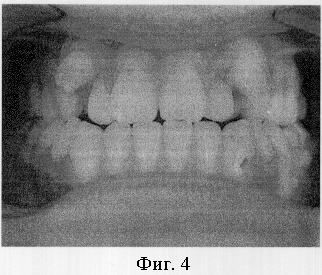

Пример 1. Пациент Б.С., 17 лет. Диагноз: дистопия верхних и нижних клыков (фиг.4). Проводилось ортодонтическое лечение с использованием брекет-системы. Клыки установлены в зубной ряд, но при этом получена значительная протрузия передних зубов и значительная вертикальная межрезцовая щель (фиг.5).